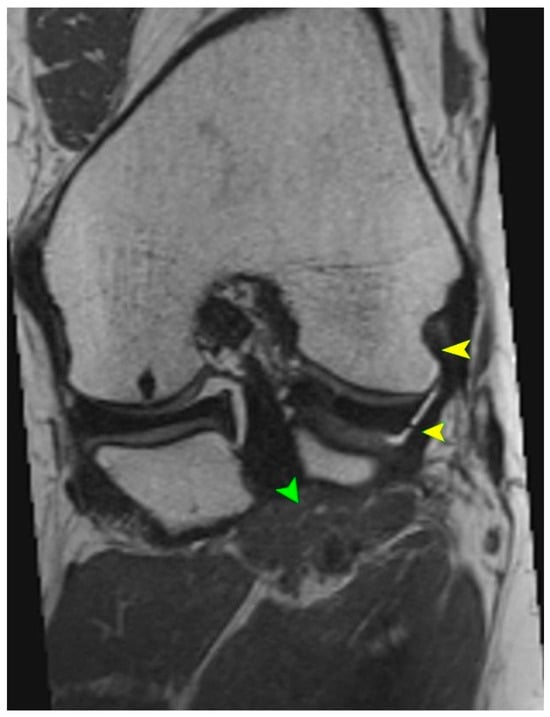

MRI is the gold standard for evaluating soft tissue structures in the knee, including the PT. Optimal visualization of the tendon is achieved using T1 and T2 weighted sequences (Figure 1 and Figure 2) with fat saturation in axial, coronal, and sagittal planes. The PT appears as a low signal intensity structure running obliquely from the lateral femoral condyle to the posteromedial tibia [1,15].

(a) Axial T1-weighted MRI showing the muscle belly of the popliteus muscle (green arrowhead). (b) Coronal T2-weighted MRI illustrating the tendinous portion of the popliteus (yellow arrowhead). Both panels demonstrate anatomical relationships of the popliteus tendon complex relevant for imaging-based identification.

Particular attention must be given to morphological variations. The presence of bifid tendons or accessory bands (Types II–IV according to Olewnik’s classification) can be mistaken for tendon ruptures, scar tissue, or pathological adhesions [11]. Recognition of these variants is essential to avoid misdiagnosis.

In acute traumatic cases, key findings include hyperintensity within the tendon on T2 weighted images, peritendinous fluid, discontinuity of tendon fibers, and surrounding soft tissue edema [1]. MRI can also reveal the secondary signs of PT injury, such as displacement of the lateral meniscus, stretching of the fibular collateral ligament, and abnormal tibial rotation [15]. Studies have shown that awareness and identification of the anatomical variability of the PT during MRI interpretation of acute knee injuries can improve diagnostic sensitivity and specificity by 15–20% [6].

While MRI provides detailed visualization of the PT and its insertion, it may not always detect fine accessory structures, especially when they are obliquely oriented or overlap with surrounding soft tissue planes [30]. By contrast, high-resolution dynamic ultrasound has been shown to detect accessory bands with greater sensitivity, especially those inserting into the lateral meniscus or fibular collateral ligament [11,31].

Recent comparative studies have suggested that an MRI achieves higher specificity (~95%) for full-thickness tears and deep tissue involvement, while a dynamic ultrasound offers superior sensitivity (~88–92%) for variant morphologies and dynamic instability patterns [30]. When used together, these imaging modalities provide complementary insights, enhancing diagnostic accuracy in both acute and chronic posterolateral pathology.